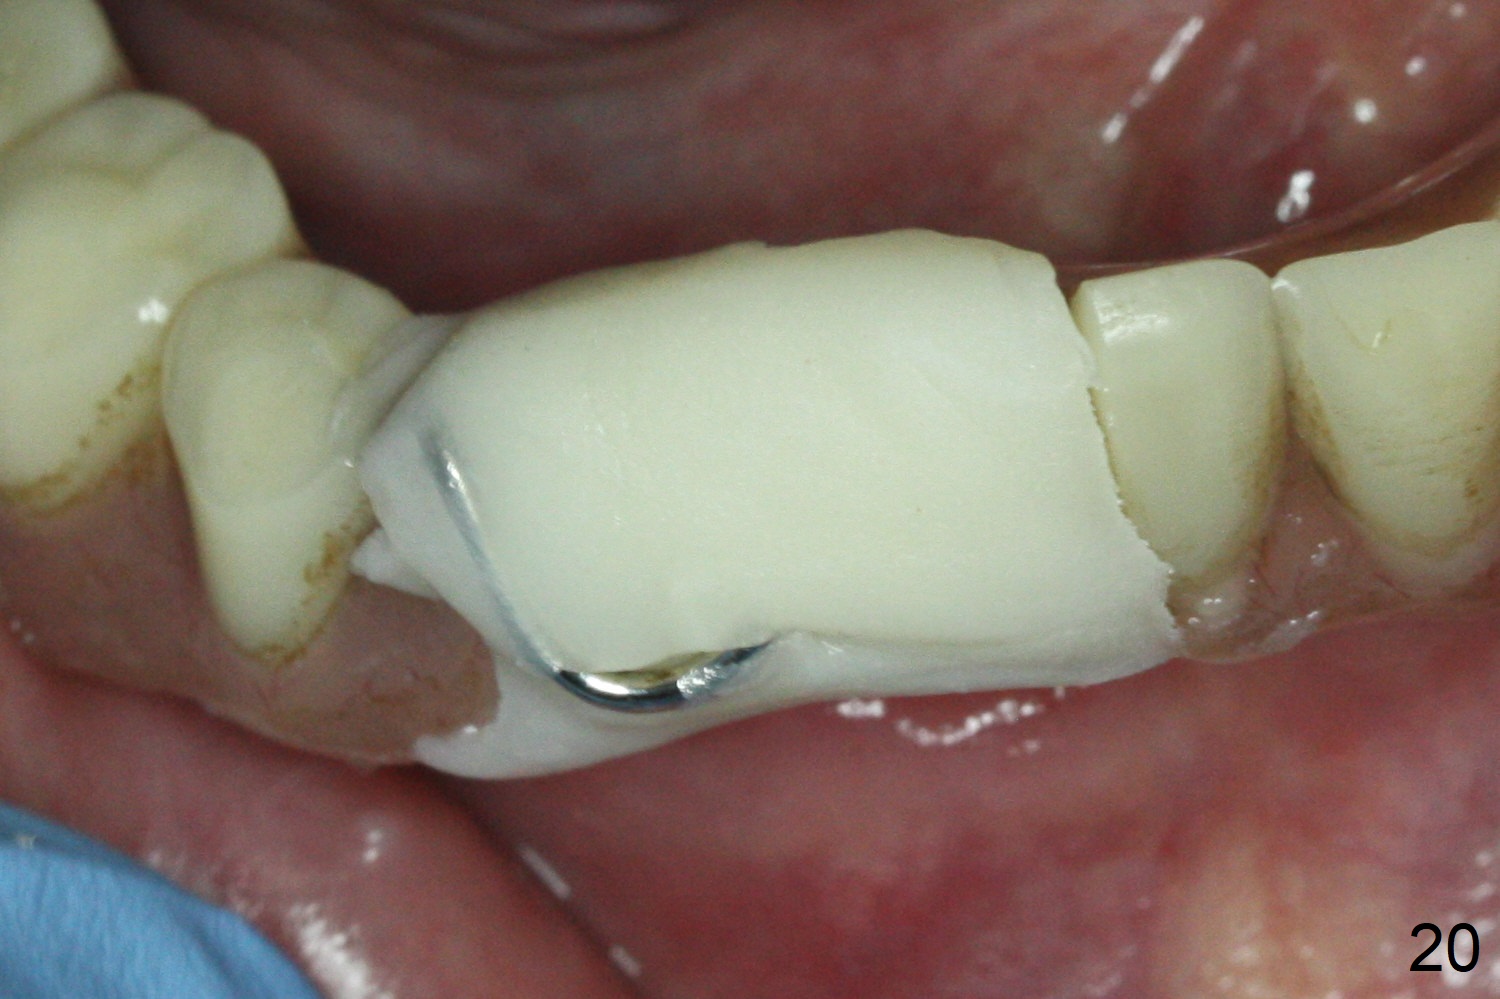

After change in abutment at #27 and abutment height adjustment at #26 and 27 (Fig.13), splinted provisional is fabricated with clearance from the RPD (Fig.14) and seal of the sockets (Fig.15). Acute submandibular and submental cellulitis develops with sublingual purulent discharge 1 month 10 days postop (Fig.16). CT confirms lingual plate perforation at both sites (Fig.17,18; red line: original socket). With block anesthesia, removal of these implants causes mild discomfort. With Hydrogen Peroxide and normal saline copious irrigation, pain reduces when anesthesia subsides. Bone graft will be placed at the sites approximately in 2 weeks. In fact the infection is not controlled until 2 weeks later (Fig.19). The clasp has to be covered with acrylic for comfort (Fig.20). The previous implant sites heal 1.5 months post implant removal (Fig.22).